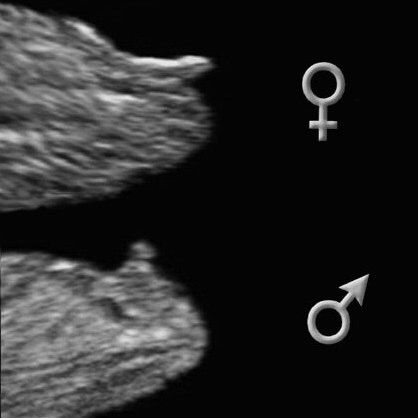

Z fotky z profilu se to nedá poznat. Nemáš přímo ultrazvuk dolních partií? 🙂 Nám doktor vyfotil přímo genitálie.

@martina_cz díky, přesně tuhle fotku sem sem chtěla dát, to jen k tématu, že se pohlaví nedá poznat z profilu. Vid, že je to jasná pipka :D ♥